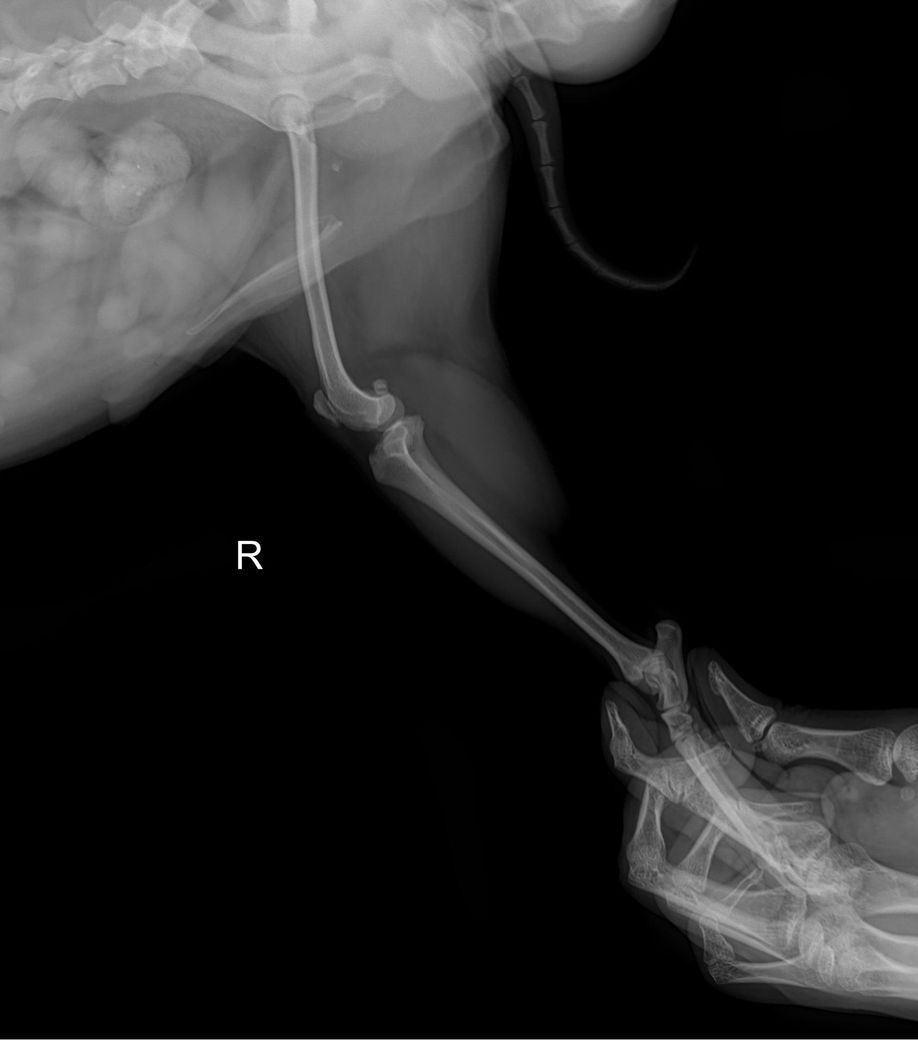

좌측 슬개골이 내측으로 탈구되어 있는 상태이며.

외측상에서 슬관절 관절낭의 종창이 뚜렷하게 관찰되어 슬개골 탈구와 함께 십자인대의 부분적 손상 가능성이 강력히 의심됩니다. 주치의의 지시대로 빠르게 수술 진행하는게 도움이 됩니다.